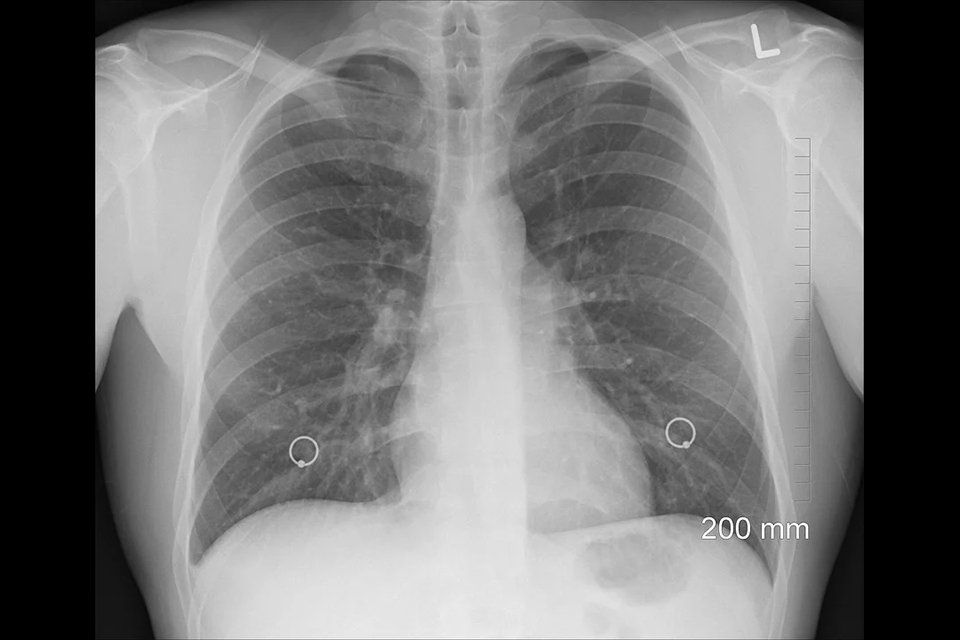

肺癌常見迷思3:肺部篩檢做胸腔X光攝影就夠了?

透過胸部X光攝影可觀看肺部是否有明顯異常,如肺炎、肺結核、肺癌、肺氣腫、肺積水、氣胸等各種肺部病變。

但蔡聰聰醫師指出由於肺癌早期不易察覺,僅靠胸部X光檢查是無法揪出微小病灶,難以偵測到1公分以下的肺部病變,也會因病灶生長位置在心臟後方、橫膈部位、或與肋骨陰影重疊處造成偵測盲點。